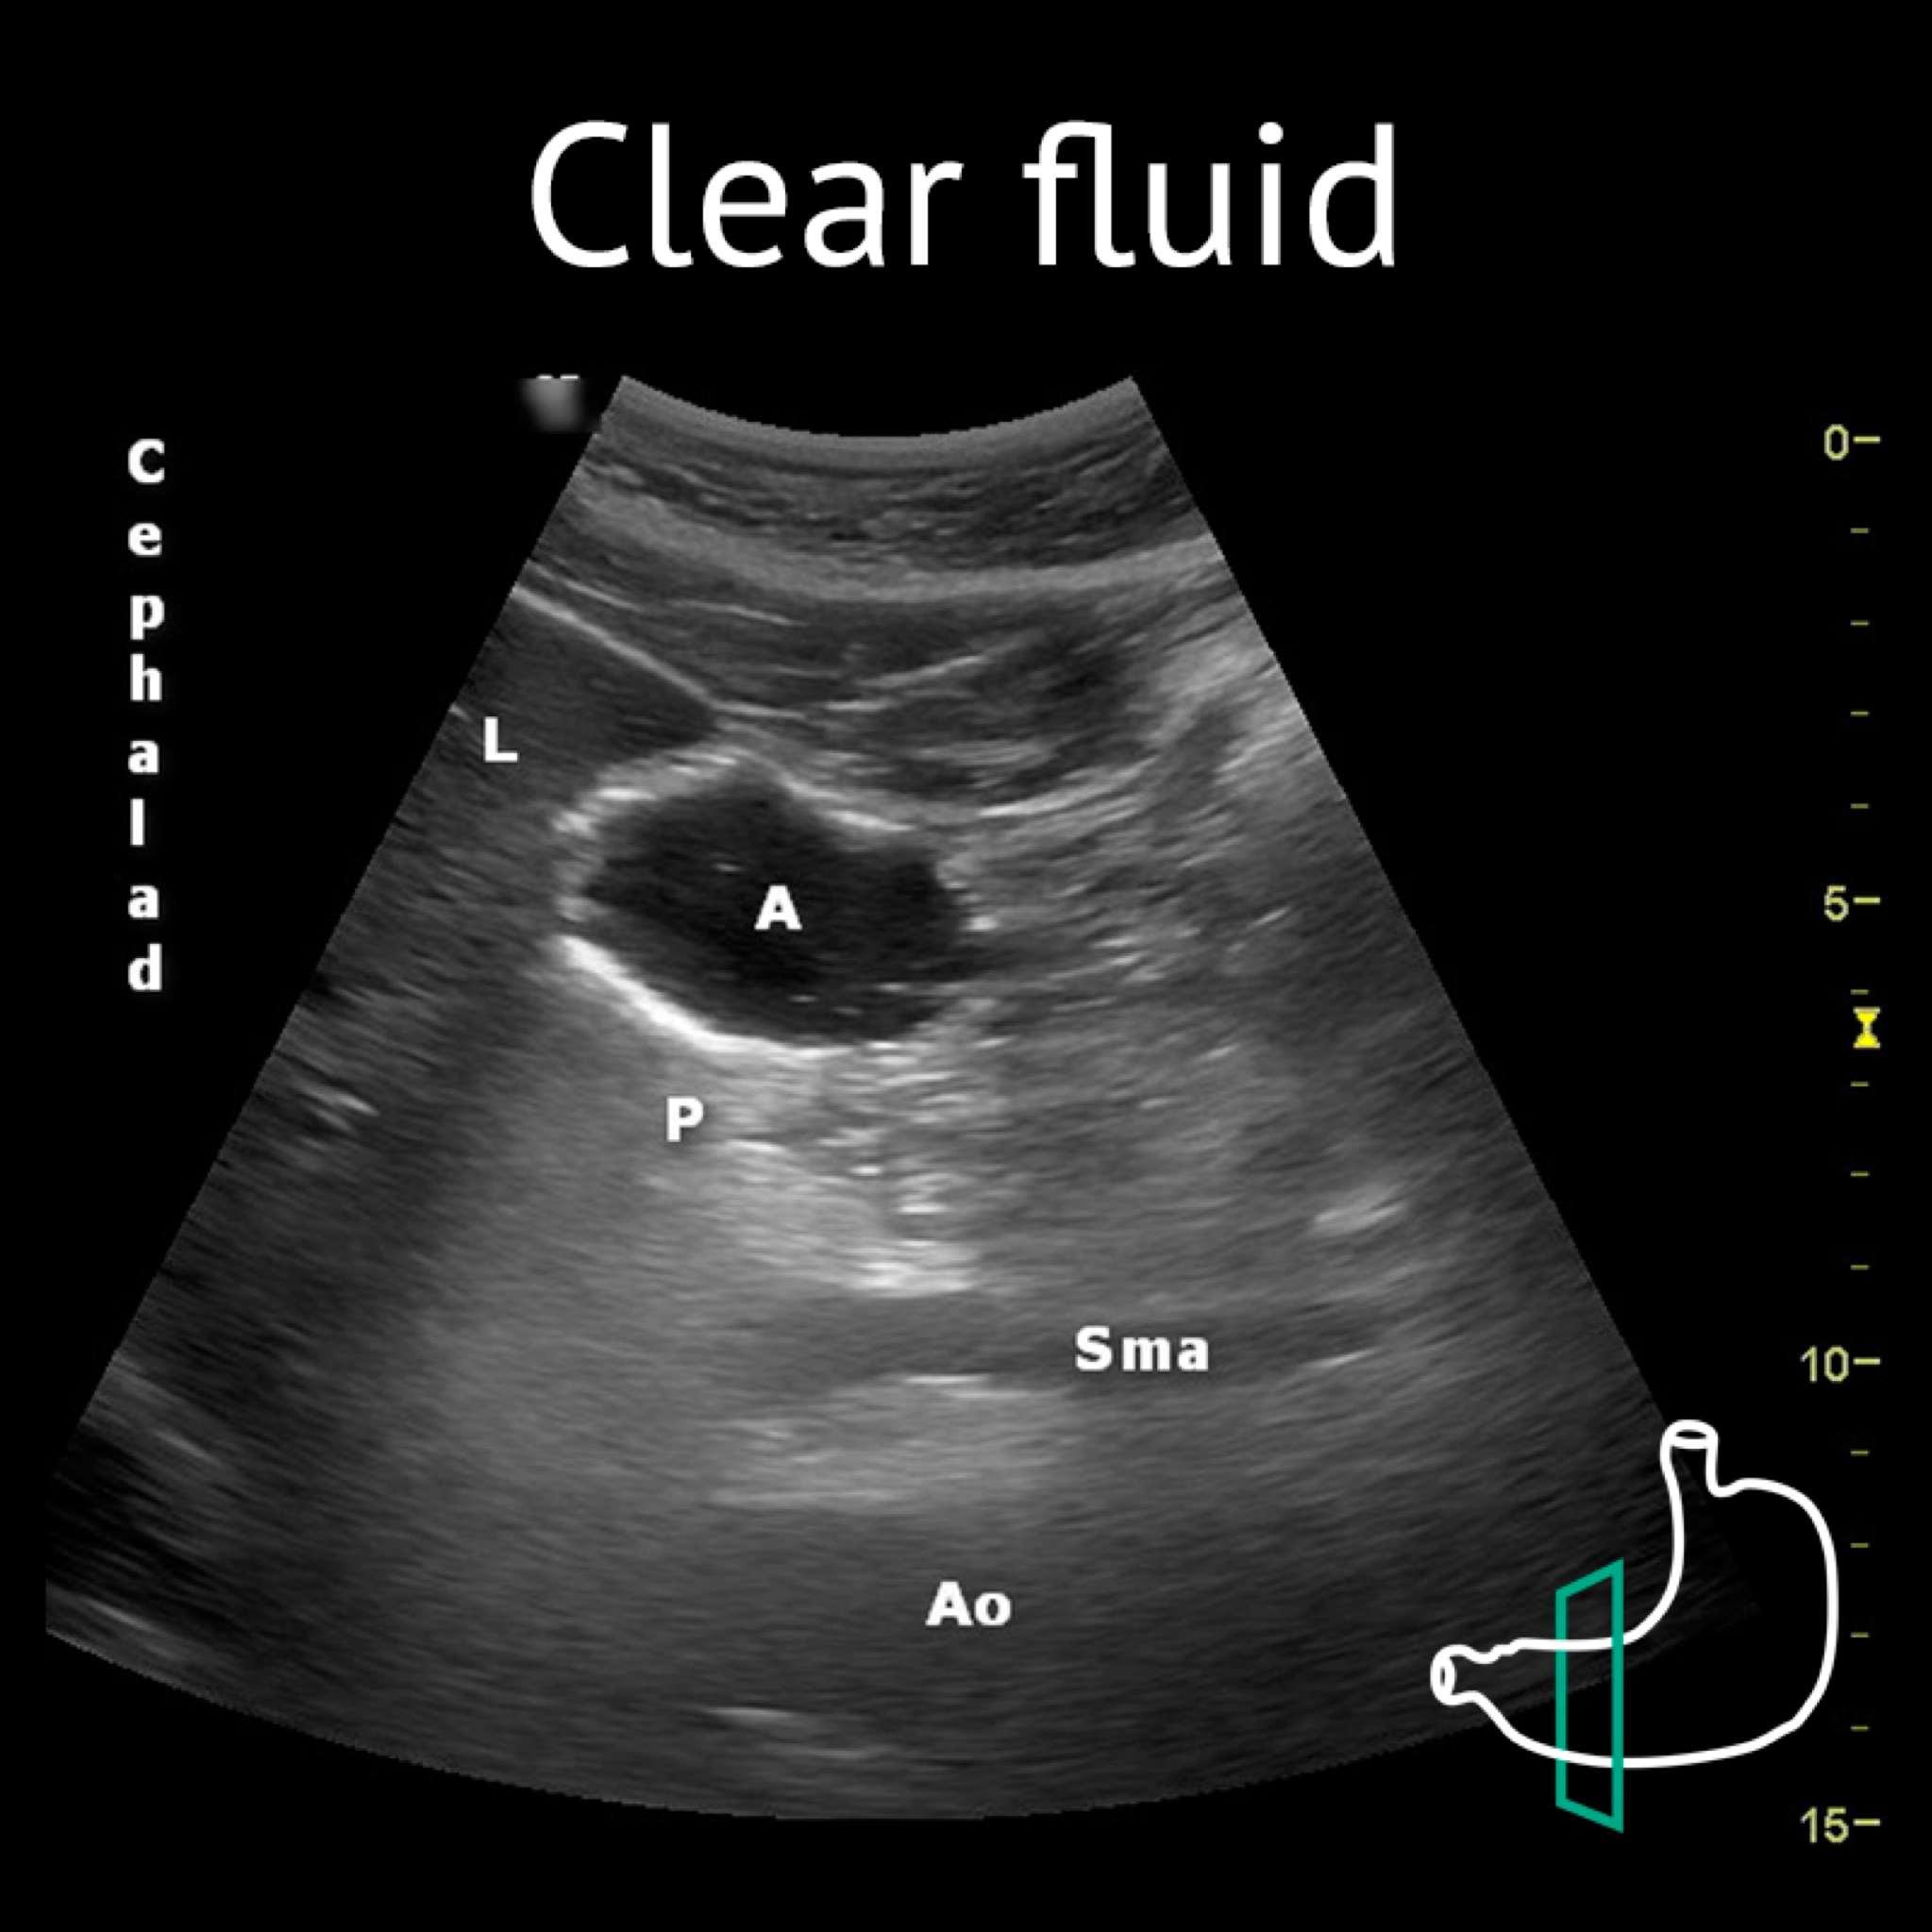

A: antrum; Ao: aorta; L: liver; P: pancreas; Sma: superior mesenteric artery